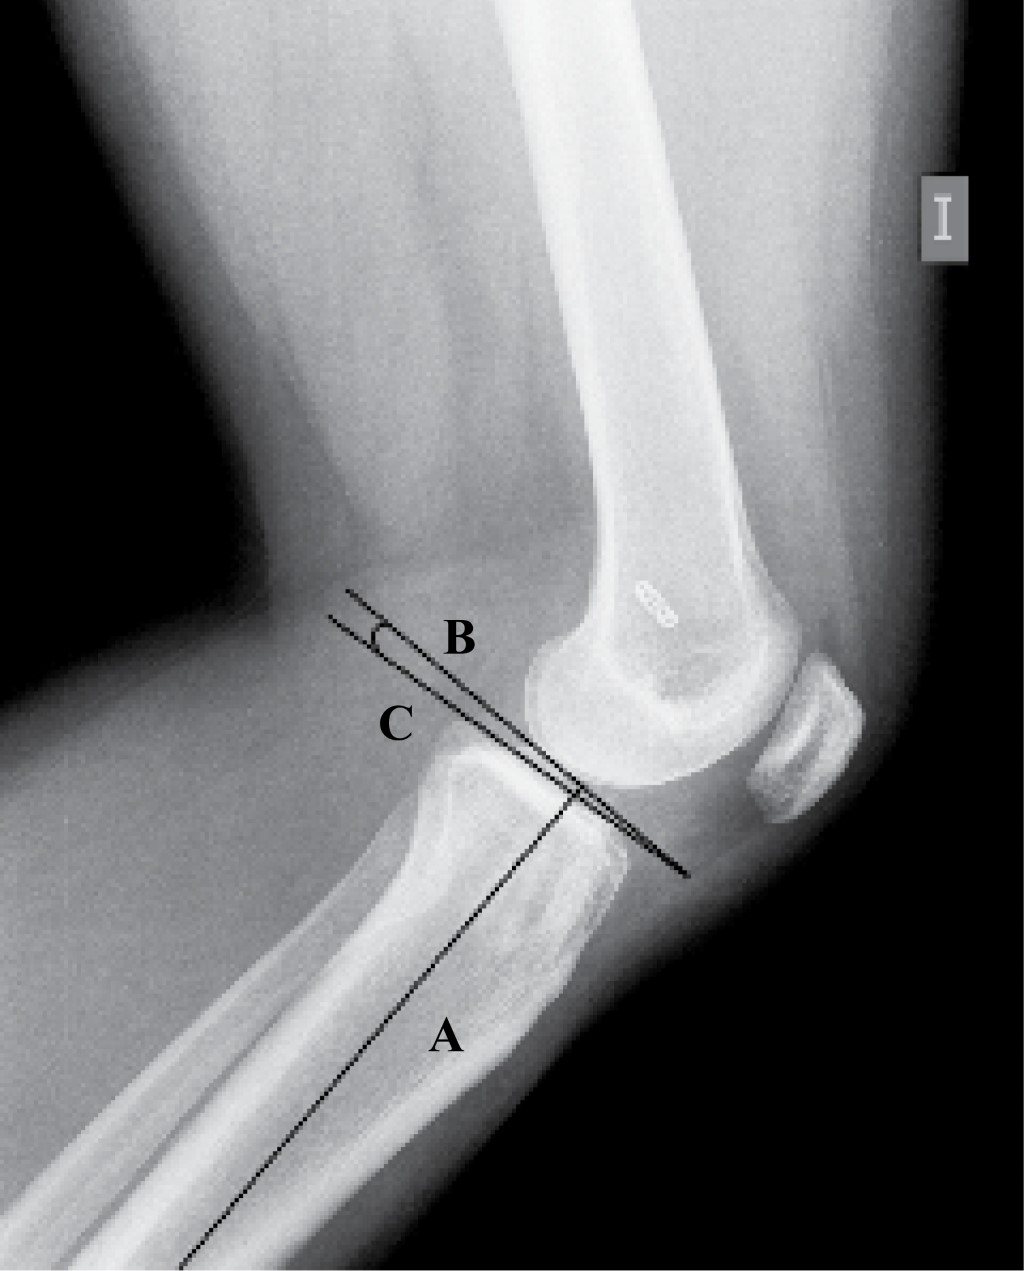

Figure 1